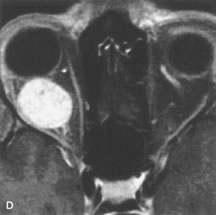

PATIENT PREPARATION Before MRI is performed, patients must be screened and prepared to avoid the potential hazards associated with the strong magnetic field. Patients who have ferrous aneurysm clips or cardiac pacemakers, who depend on life-support equipment, or who retain a possible metallic intraocular foreign body are not candidates for this imaging modality. MRI cannot be performed on obese patients who cannot fit into the bore of the magnet. Patients who are claustrophobic may not tolerate a prolonged period of study within the confines of the magnet, whereas others might do well if given a mild sedative. All worn metallic objects (e.g., necklaces, watches) should be taken off, credit cards set aside, and eye makeup removed before entering the room containing the magnet.5,20,34,35,36 NORMAL ORBITAL ANATOMY T1-weighted images provide the best anatomic details of the orbit because they display superior contrast resolution between normal structures (see Fig. 8). The vitreous has a long T1, resulting in an intermediate signal similar to brain, whereas the crystalline lens and sclera appear dark because of a longer T1 and short T2. The extraocular muscles, like all skeletal muscles, demonstrate a moderately long T1 and short T2 and highly contrast with the intense signal of the surrounding orbital fat (adipose tissue has an extremely short T1). The lacrimal glands appear as mottled areas of reduced intensity of the signal from the orbital fat in the lacrimal fossa. The optic nerves are seen with the same signal intensity as brain white matter and are hypointense relative to the orbital fat because their Tl is longer than the Tl of fat but shorter than the Tl of water. Cortical bone is not well delineated because it contains little free water, yielding minimal signal in MRI, and thus appears dark on all pulse sequences. This feature explains why MR images of the orbital apex and intracanalicular portion of the optic nerves are superior to comparable CT scans. Partial volume averaging of the bones in these regions obscures soft tissue details on CT images, whereas MRI reveals the signals only from the soft tissue structures with no cortical bone input. Bone marrow, on the other hand, is seen as a relatively intense signal because of its high fat content (see Fig. 8).37,38 T2-weighted pulse sequences are not ideal for imaging normal anatomy; however, they are particularly useful in revealing pathologic conditions (see Fig. 9). T2-weighted studies are most easily recognized by a bright vitreous signal. ORBITAL DISEASES Vascular Lesions Cavernous hemangiomas appear as well-circumscribed, smooth, usually intraconal masses that are isointense to muscle on T1-weighted images and hyperintense on T2-weighted images (Fig. 12). Patchy early enhancement is typically followed by diffuse, more homogeneous enhancement.39 The internal architecture of the mass, including septation and internal vasculature, may often be appreciated with high-quality orbital imaging.40 Lymphangiomas consist of ectatic vascular channels within a connective tissue stoma with varying degrees of lymphoid cellularity. On MRI, these tumors are typically poorly circumscribed, multicompartmental, and heterogeneous, often showing cystic dilations with fluid levels (Fig. 13). The signal characteristics within lymphangiomas vary considerably, reflecting cystic and solid components and the varying paramagnetic characteristics of blood at different stages of degradation.40–42 Acute hemorrhage appears hypointense on both T1- and T2-weighted formats. Methemoglobin present in subacute hemorrhage (3 to 14 days) leads to hyperintense signal on both T1- and T2-weighted images.41 A small percentage of lymphangiomas appear radiologically indistinct from orbital cavernous hemangiomas.43 Orbital varices are venous malformations that expand with increased systemic venous pressure, such as with Valsalva maneuvers. Because rapid acquisition of images during a Valsalva maneuver is important in imaging such a lesion, conventional or spiral CT is currently the modality of choice.44 MRI is an excellent modality for demonstrating enlargement of the cavernous sinus and dilation of the superior ophthalmic vein in patients with high-flow carotid-cavernous fistulas (Fig. 14).37MRA may be helpful in the evaluation of the venous outflow pattern. The rapidly flowing blood in these vascular structures carries the excited protons out of the section before they can be imaged, resulting in their dark appearance.5 In low-flow dural arteriovenous malformations, MRA may help define the arterial feeding vessels.45 Neural Lesions MRI is more effective than CT in delineating the intracranial optic nerves, chiasm, and optic tracts and, for this reason, is the preferred imaging modality in the evaluation of optic nerve disorders. The spatial relationships and image contrast of the orbital tissues with intraorbital optic nerve tumors is comparable between the two imaging modalities. The normal nerve is isointense to brain and appears enlarged and kinked owing to infiltration of an optic nerve glioma on T1-weighted images. Gliomas appear hyperintense on T2-weighted images and may be heterogeneous owing to cystic areas within the tumor. Contrast enhancement is variable.46 Intraorbital and intracranial optic nerve sheath meningiomas are usually isointense to cortical gray matter on Tl-weighted images and remain isointense on proton density studies (Fig. 15). Gd-DTPA is useful in delineating the intracranial extension of optic nerve meningiomas.7,47 The hyperostosis of bone and calcification associated with meningiomas are not demonstrated as well on MRI studies as on CT scans.20,37 Gd-DTPA–enhanced MRI also appears promising in the study of the permeability of the blood–brain barrier in selected optic neuropathies.22,48 MRI may reveal an enlarged optic nerve and some degree of contrast enhancement in cases of optic neuritis.49 Muscle Disorders Extraocular muscle enlargement in patients with thyroid-associated orbitopathy is demonstrated equally well with CT and MRI studies. However, the superior tissue contrast on MR images reveals better details of the relationships of the optic nerve to the thickened muscles at the orbital apex (Fig. 16).50 In addition, MRI may be able to differentiate between muscles that are enlarged as a result of edema and active inflammation and those enlarged because of fibrosis by their T2 relaxation times.21 Quantitative MRI was not found to be accurate in predicting the success of low-dose orbital irradiation.51 However, a muscular index relating the diameters of the rectus muscles to the bony orbital dimensions was useful in predicting optic nerve compression.52 MRI is also effective in imaging orbital tumors of mesenchymal origin, such as rhabdomyosarcoma, particularly in the assessment of extension into the anterior and middle cranial fossae (Fig. 17).37 The lack of any pathognomonic radiologic features necessitates rapid orbital biopsy when rhabdomyosarcoma is suspected. Osseous Lesions In general, CT is the imaging modality of choice when details of quantity and quality of bone are needed; however, abnormalities of bones can be detected indirectly by MRI. Cortical bone appears black (signal void) on MR images because of its low proton density and free-water content. The absence or discontinuity of the signal void of the orbital walls may represent bony destruction or fracture. Hyperostosis associated with prostate metastases or meningioma is visualized as areas of black smudging.50,53 Diseases in which the bone is replaced by pathologic tissues with a high free-water content, such as fibrous dysplasia, are well demonstrated on MRI. An intermediate signal intensity on T1-weighted images and hypointense signal on T2-weighted images is representative of fibrous dysplasia. Enhancement on post–Gd-DTPA MR scans is seen and is more evident in areas that are less mineralized.54 Cystic Lesions Dermoid cysts appear as rounded, well-defined lesions typically contiguous with an orbital bony suture. The high-intensity signal on T1-weighted images is attributed to the sebaceous-produced lipid contents (Fig. 18).31,50 Mucoceles may demonstrate a hypointense or hyperintense signal on MR images, depending on the concentration of proteinaceous or inflammatory fluid components. The integrity of the bony walls of the expanded sinus cavities cannot be assessed on MR as well as by CT.37,50,55,56 A high-signal intensity on Tl- and T2-weighted images is characteristic of orbital chronic hematic cysts because of the blood-breakdown products within the cysts.57 Trauma Although soft tissue relationships are usually better demonstrated on MRI, the evaluation of craniofacial bony trauma is preferable with CT. For example, prolapse of orbital fat through a fracture site and hemorrhage of adjacent tissues are demonstrated in an MR image, but the actual fractured bone is not imaged. Three-dimensional MRI of the orbit in subacute trauma has been described,58 although its precise role is not currently established. MRI has been suggested to be superior to CT in detecting intraorbital wooden foreign bodies.59,60 In a series of penetrating orbital injuries with organic foreign bodies, however, MRI was able to identify the foreign body in only four of seven cases.61 With an in vitro model for wood foreign body, McGuckin and colleagues concluded that CT was the imaging modality of choice.62 A careful history and, in selected cases, plain films to rule out a metallic foreign body are crucial before MRI is considered in patients with periocular trauma. MRI is particularly helpful in the detection and characterization of subperiosteal hematomas of the orbit (Fig. 19). They are most commonly seen in the subperiosteal space of the superior orbit as well-defined masses following a traumatic injury. The signal intensity varies depending on the acute, subacute, or chronic nature of the hematoma, based on the stage of blood degradation. Fresh hemorrhages are hypointense on T1-weighted images and hyperintense on T2 images. Hematomas that are 1 to 7 days old are hypointense on both T1- and T2-weighted images. T1-weighted images of hematomas more than a week old are hyperintense due to the oxidation of deoxyhemoglobin to methemoglobin, whereas the T2 images remain hypointense.63 Metastatic Tumors Breast carcinoma metastatic to the orbit has been demonstrated to be hypointense to the surrounding orbital fat on T1-weighted studies and hyperintense on T2-weighted images and has an affinity to the extraocular muscles (Fig. 20).50,64 The MRI characteristics of prostate carcinoma metastatic to the orbit have been described as involving the greater and lesser wing of the sphenoid, orbital roof, and optic canal. Diffuse bone hypertrophy with isointense or slightly hyperintense tissue on T1-weighted images represents the osteoblastic carcinomatous bone infiltration. Contrast enhancement is variable on T1-weighted and fat-suppressed images.65 Most other metastatic tumors also have a lower intensity signal on T1-weighted images and appear to displace or infiltrate normal orbital structures; however, their signal characteristics are variable on T2-weighted MR images.66 Many metastatic tumors demonstrate bright contrast enhancement with Gd-DTPA. Infectious Disorders MRI findings of preseptal and orbital cellulitis typically include increased signal intensities on T2-weighted images of the eyelids and orbital fat, respectively, due to the increased water content of the tissues. Since most cases of bacterial orbital cellulitis are associated with paranasal sinusitis, hyperintense signals of the affected sinuses may also be found on T2-weighted images as well as enhancement of polyps and granulation tissue on postgadolinium T1-weighted MR images. Subperiosteal abscess formation may occur due to contiguous spread of infection from the paranasal sinuses and appear on MRI as an area of intermediate signal on T1-weighted and proton-weighted MR images. The abscess may appear slightly hyperintense compared with muscle on T2-weighted scans with the necrotic contents having the greatest intensity.67 MRI and MRV are more sensitive than CT in revealing cavernous sinus thrombosis. Engorgement of the cavernous sinus, extraocular muscles, and ophthalmic veins is seen with hyperintensity of the thrombosed sinuses evident on all pulse sequences. The enlarged, thrombosed superior ophthalmic vein appears less hypointense than the normal contralateral ophthalmic vein, and hyperintensity within the lumen of the vessel may be seen on T1- and T2-weighted MR images.68 Inflammatory and Lymphoproliferative Lesions Inflammatory conditions of the orbit, both idiopathic (inflammatory pseudotumor) and those of known causes, have been found to be hypointense to fat and isointense to muscle on Tl-weighted studies and isointense or slightly hyperintense to fat on T2-weighted images (Fig. 21).50,64,69 The more fibrous or sclerosing varieties have less signal intensity on T2-weighted images. Marked enhancement is seen in pseudotumor infiltrates after gadolinium administration.70 The same signal characteristics are demonstrated in patients with Tolosa-Hunt syndrome, with mass lesions seen in the cavernous sinuses and orbital apices.71 Lymphomas have MRI characteristics similar to those of inflammatory lesions in that they are hypointense to fat and isointense to muscle on T1-weighted images (Fig. 22). They may appear hyperintense to fat on T2-weighted images, perhaps owing to less fibrosis than that seen in orbital inflammatory pseudotumor, although this is not a consistent finding.31,50,66 Lymphoid tumors typically enhance moderately after contrast injection. Unfortunately, studies have shown that tumor density and homogeneity are similar between inflammatory and malignant orbital infiltrates, and MRI cannot differentiate these lesions.72,73 Lacrimal Gland Tumors Lacrimal gland lesions present special problems in diagnosis and management. Pleomorphic adenoma (benign mixed tumor) should not be biopsied, but rather excised in toto. On the other hand, for lymphoma and inflammatory infiltrates, incisional biopsy is more appropriate than complete excision of the lacrimal gland. Thus, preoperative clinical and radiologic evaluation are especially crucial in planning appropriate surgical management. Pleomorphic adenomas demonstrate long T1 and T2 signal characteristics. They may show heterogeneity on T2-weighted images74 and moderate to marked enhancement with contrast.75 Signal characteristics of adenoid cystic carcinoma include hypointensity to fat on T1-weighted images, hyperintensity to fat with increased T2 weighting, and isointensity to fat on proton density-weighted studies (Fig. 23).31,75 Secondary bony alterations of the lacrimal fossa associated with lacrimal gland tumors, such as remodeling (benign mixed tumor) or destruction (adenoid cystic carcinoma), are seen indirectly on MR images; however, bone windows on CT scans provide better delineation of these changes. In contrast to the round or globular appearance of benign or malignant epithelial tumors of the lacrimal gland, lymphoproliferative tumors usually appear to be molding or draping onto the globe and the surrounding bony orbit. LACRIMAL DRAINAGE SYSTEM DISORDERS MRI with surface coils provides excellent spatial resolution and tissue-specific signal intensities of the lacrimal drainage system. These parameters have been found useful to more accurately demonstrate the extent of lesions in the lacrimal sac and differentiate long-standing mucoceles from solid tumors than CT.76 Physiologic studies in patients with tearing disorders now include MR dacryocystography, in which Gd-DTPA is either placed topically in the conjunctival fornix or injected by cannulation into the lacrimal sac. They provide a detailed morphologic and functional analysis of the lacrimal excretory system; however, they are no more sensitive than digital-subtraction dacryocystography or CT dacryocystography.77–79 INTRAOCULAR TUMORS On MRI, uveal melanomas have a typical appearance that helps to differentiate them from other primary and secondary intraocular tumors as well as choroidal detachments. Pigmented melanomas are hyperintense on Tl-weighted images, hypointense on T2-weighted studies, and hyperintense on proton density–weighted examinations (Fig. 24).30,31,50,80–82 These signal characteristics have been attributed to the paramagnetic properties of melanin because of stable free radicals that shorten the T1 and T2 relaxation times. Moderate enhancement is seen on postgadolinium T2-weighted images. Gadolinium-enhanced T1-weighted images are particularly sensitive in detecting choroidal melanomas.83 MRI may be less sensitive in detecting extrascleral extension of tumor than echography performed by an experienced ultrasonographer.84 Tumors metastatic to the choroid are hyperintense on T1- and T2-weighted images.24 The signal characteristics, however, may be similar to those seen with choroidal melanoma. Choroidal hemangiomas, on the other hand, have an intermediate signal on T1-weighted sequences and become hyperintense on T2-weighted images50 as well as proton density–weighted images.81 Retinoblastomas display moderate signal intensity on T1-weighted studies and a low signal on T2-weighted images.31,80,85 Calcification can be easily detected by CT and ocular ultrasonography but is not imaged by MRI.25,50 The presence of optic nerve involvement is best evaluated by MRI. ACQUIRED ANOPHTHALMIA When an eye is removed owing to tumor or trauma, an implant is typically placed in the intraconal space. MRI may be useful in defining the size, shape, and position of such orbital implants.86 Porous hydroxyapatite or polyethylene implants are preferred by many surgeons performing enucleation or evisceration. A porous implant offers the possibility of supporting a motility coupling peg to increase the movement of the overlying prosthesis. MRI with contrast is used by some surgeons to evaluate the degree of fibrovascular ingrowth in hydroxyapatite87 and porous polyethylene88 implants prior to motility peg placement. |